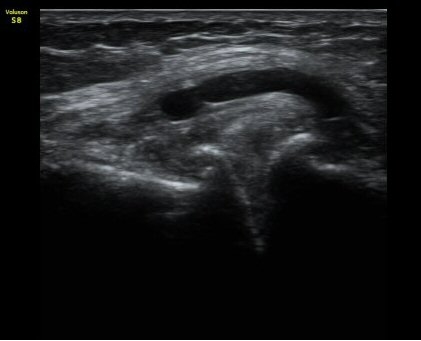

¹«¸­ ³»Ãø Á¾´Ü¸é°Ë»ç¿¡¼­ °üÀý°£°ÝÀÇ °¨¼Ò ¹× ¹Ý¿ùÆÇ¿¬°ñÀÇ ÅðÇ༺ º¯È­¿Í ¿ÜÃø À¸·Î µ¹Ãâ¿¡

ÀÇÇÑ ³»Ãø ÃøºÎÀδëÀÇ ½ÉÇÑ ¿ÜÃø µ¹Ãâ º¯ÇüÀ» º¸ÀÌ°í ³»Ãø ÃøºÎÀδë¿Í ¹Ý¿ùÆÇ¿¬°ñ »çÀÌ¿¡ ¹«¿¡ÄÚ

¼ö¾× Àú·ù°¡ °üÂûµÊ. °æ°ñ°ú ´ëÅð°ñÀÇ °ñ±ØÀÌ ¸Å¿ì ½ÉÇÑ »óÅÂÀÓ(±×¸² 1, 2).